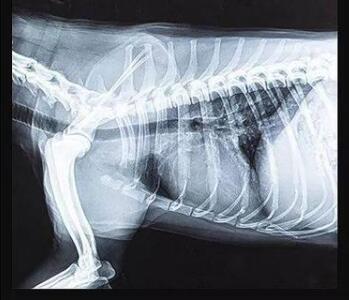

传统的平板探测器,相当于普通摄像机,对于拍摄急促呼吸状态下的宠物,成像效果存在着明显缺陷。而新一代宠物平板探测器,宛如高速摄像机,能够清晰记录动物每一个精准瞬间。

宠物dr专用平板拍摄效果